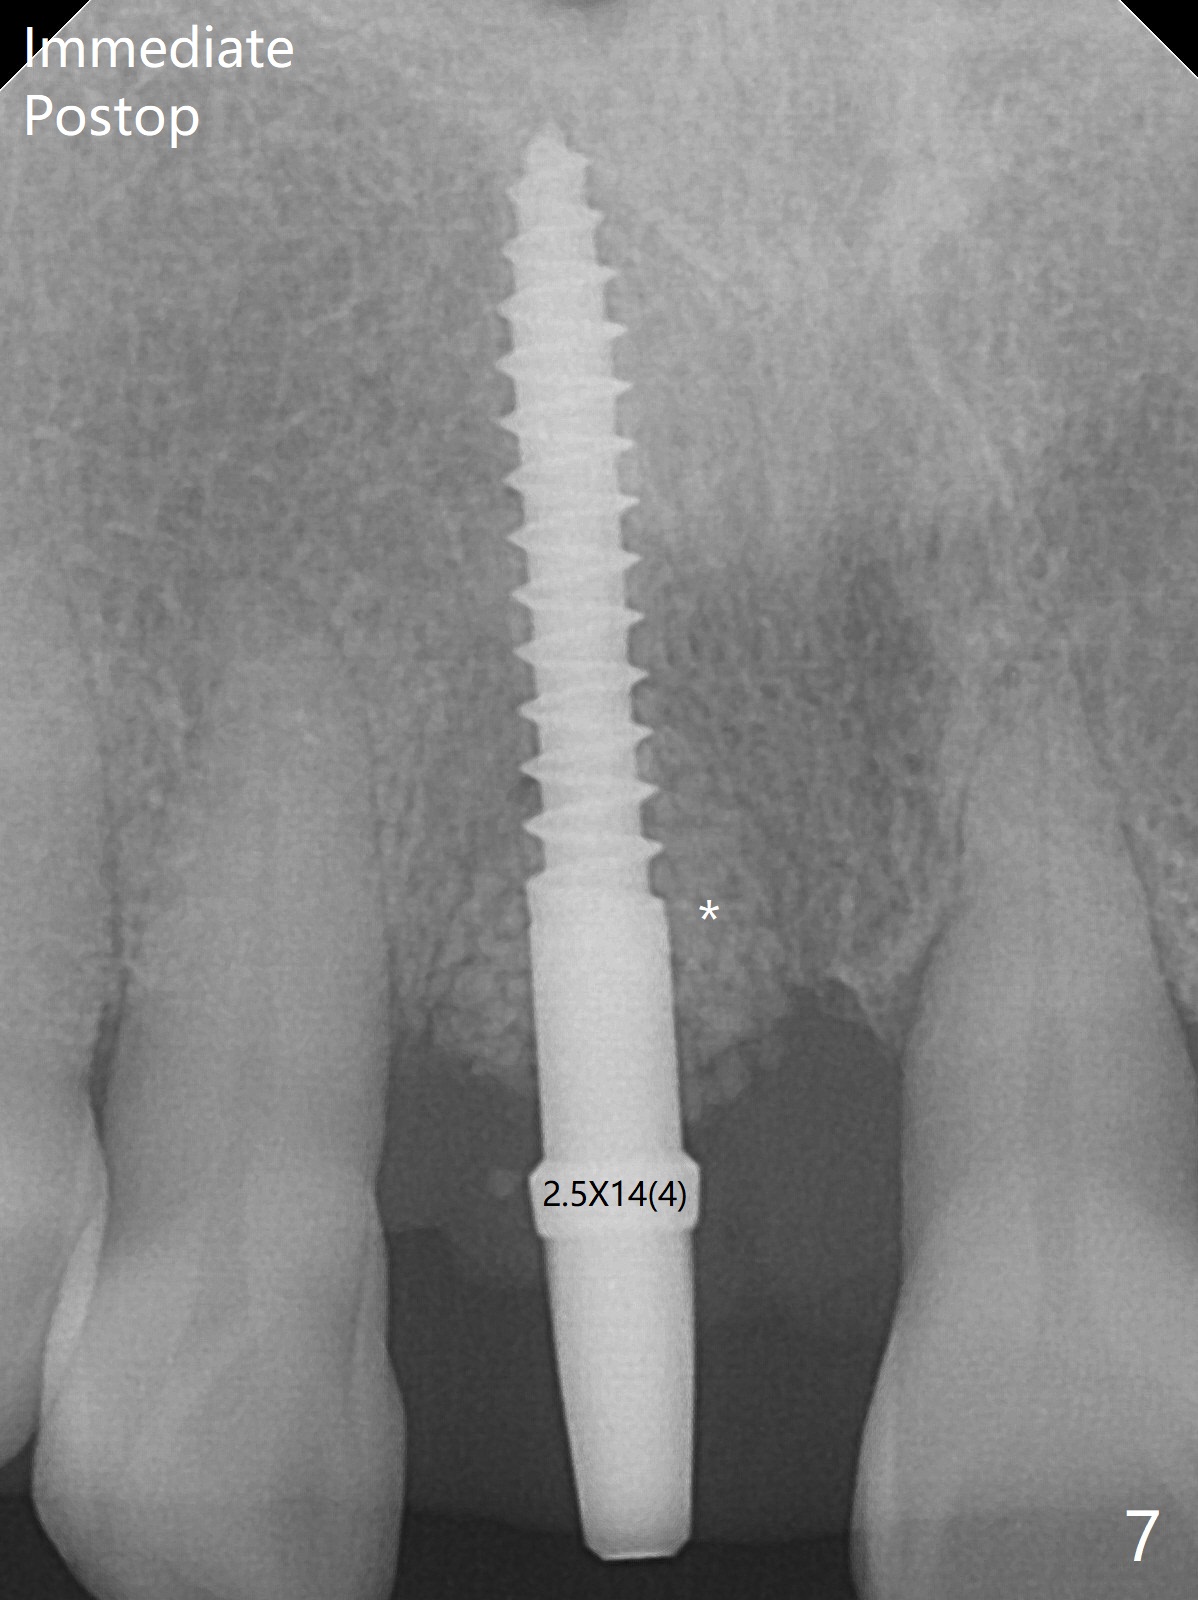

59岁女术前右下1,2切缘磨短后,右上1颊侧移位得到纠正(图一(咬合创伤))。拔牙后证实颊侧骨板缺失,钻洞始于腭侧(图二),当1.5毫米钻头感觉刚穿破鼻底时,置入2.5x14(4)毫米一段式植体,好像进入鼻腔,但是扭力<10Ncm(图三)。把一张PRF膜放入牙槽窝,一端紧贴颊侧牙龈腭侧,另一端放置颊侧牙龈颊侧(图四),然后开始用粘性骨粉(图五,七:*(100%皮质骨))充填颊侧间隙。后者填满时(图五:*),将外面一端PRF翻转覆盖牙槽窝开口,并插入基台固定(图六),最后插入龈下,用临时牙冠固定(图八(T),九(*:PRF))。术后九天牙龈退缩(图十:^),临时牙冠突出(*),后者龈缘和切缘进行调整,缩短(图十一,十二),少许骨粉暴露(图十二:>),十四天后牙龈往下生长,好像形成角化龈(图十三:*)。